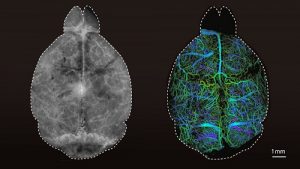

Mehr erfahren zu: "Blick in die Tiefen des Gehirns" Blick in die Tiefen des Gehirns Forschende der ETH Zürich und Universität Zürich um Daniel Razansky haben eine neue Mikroskopietechnik entwickelt, die Prozesse im Gehirn in hochauflösenden Bildern sichtbar macht. Damit können kognitive Funktionen und Krankheiten […]